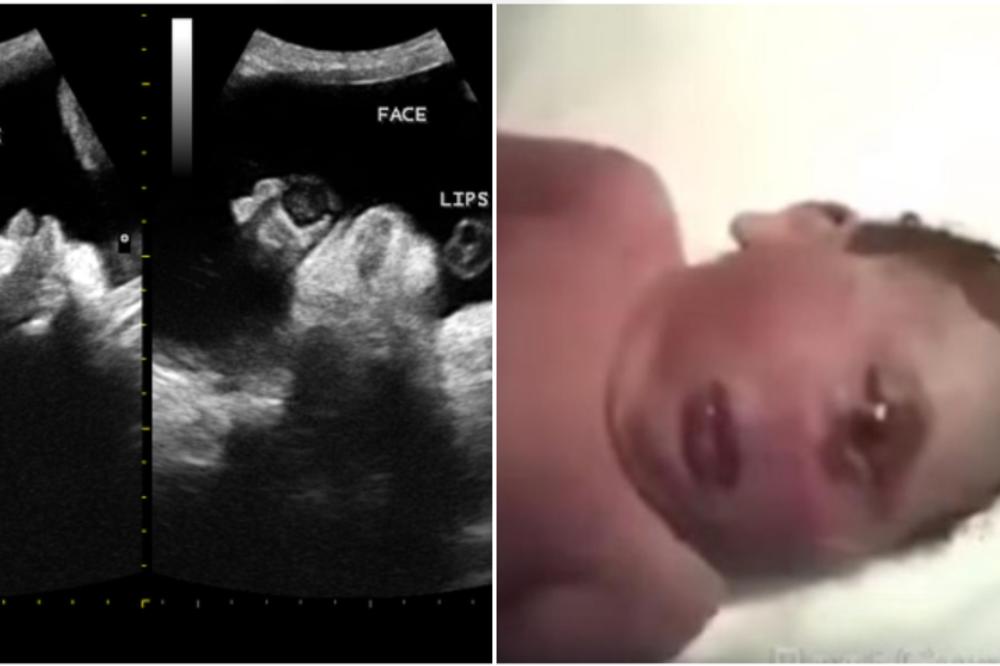

Dodaje kako se uz to najčešće nađe i čitav niz drugih malformacija i to prvenstveno mozga, teške malformacije nosa i usne šupljine koje onemogućavaju disanje, te bubrega, srca i prstiju. Učestalost kiklopije je oko 1:100 000 novorođene dece (od kojih je deo mrtvorođen).

O detetu rođenom s kiklopijom pisali su i stručnjaci na US National Library of Medicine. To dete se rodilo u Vojnoj bolnici Pince Hashem u gradu Zarga u Jordanu s težinom od 2900 grama. Rodila ga je 18-godišnja žena.

Bila je to prva beba u toj porodici, a da s njom nešto nije u redu saznali su na ultrazvuku u ranoj trudnoći. Nesrećno dete je imalo jedno oko, nos mu je nedostajao, imalo je nekoliko deformacija na abdomenu i još neke nepravilnosti u razvoju. Živelo je svega pet sati.

U Indiji je 2006. godine rođena beba koja je uspela da preživi mesec dana, a pet godina nakon toga tamo je rođeno još jedno dete s ovim poremećajem koje je živelo svega jedan dan.